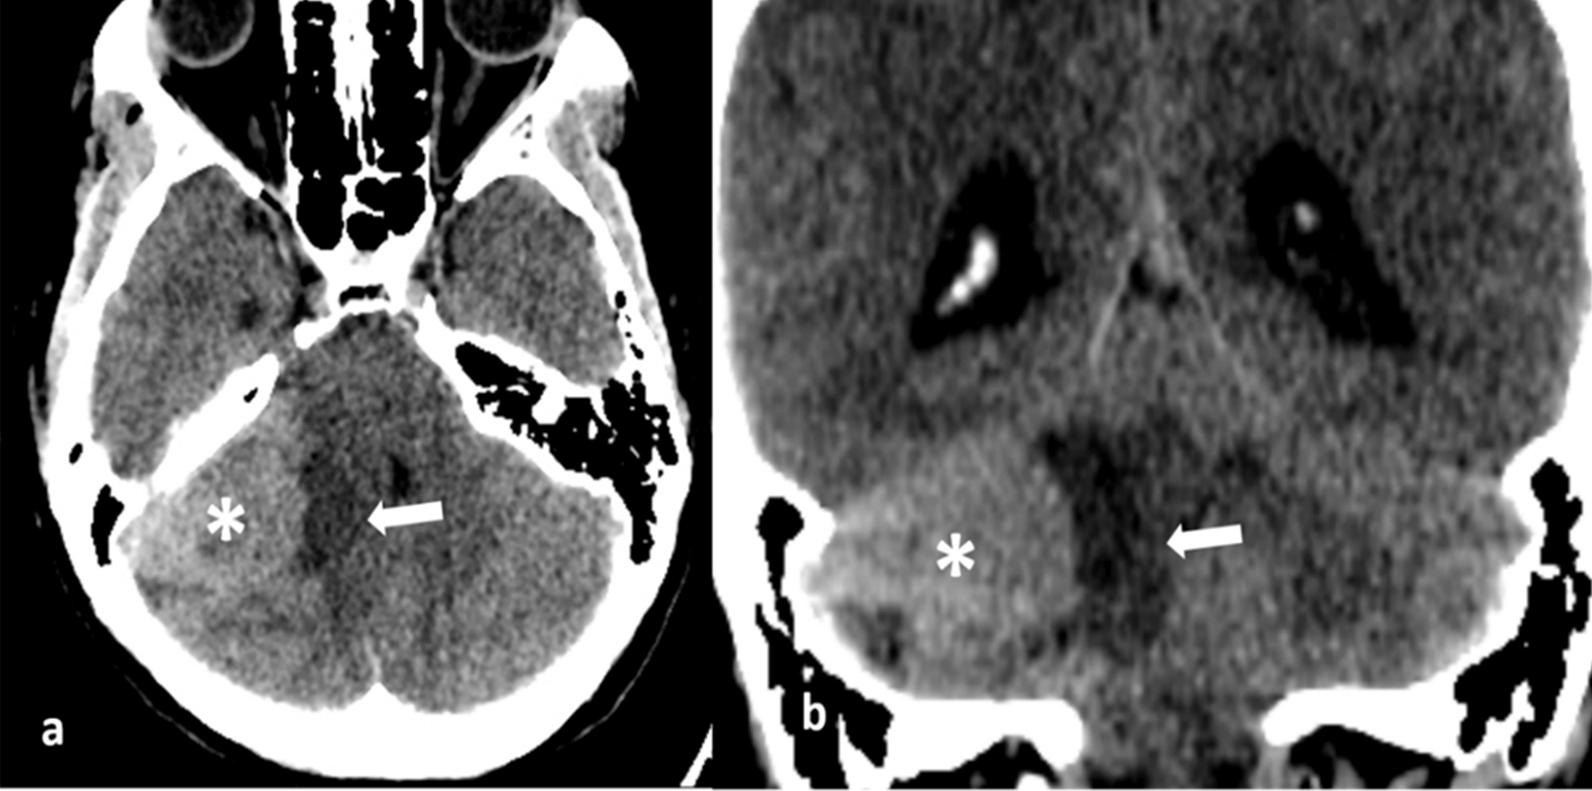

We present the unique case of a 39-year-old woman of Asian descent who suffered from headaches and right-sided hearing impairment. A right extra-axial medulloblastoma with an extremely low apparent diffusion coefficient of 0.404 × 10 mm/second was detected on magnetic resonance imaging. The initial diagnosis suggested schwannoma or hemangioblastoma. However, the postoperative histopathologic findings indicated medulloblastoma (World Health Organization grade IV). Pre- and postoperative magnetic resonance imaging revealed no drop metastasis, but adjuvant radiation therapy was still required as a standard treatment therapy CONCLUSIONS: Extra-axial medulloblastoma is an uncommon tumor that is often mistaken for other cerebellopontine angle neoplasms. We describe a rare example of extra-axial medulloblastoma, characterized by a low apparent diffusion coefficient. When evaluating an atypical cerebellopontine angle neoplasm, the apparent diffusion coefficient should be considered a relevant indicator.

我们介绍了一个独特的病例,一名 39 岁的亚洲女性,患有头痛和右侧听力障碍。磁共振成像显示右侧脑外髓母细胞瘤,表观弥散系数极低,为 0.404×10mm/秒。最初的诊断提示神经鞘瘤或血管母细胞瘤。然而,术后组织病理学检查结果提示为髓母细胞瘤(世界卫生组织 4 级)。术前和术后磁共振成像均未显示有肿瘤转移,但仍需辅助放疗作为标准治疗。